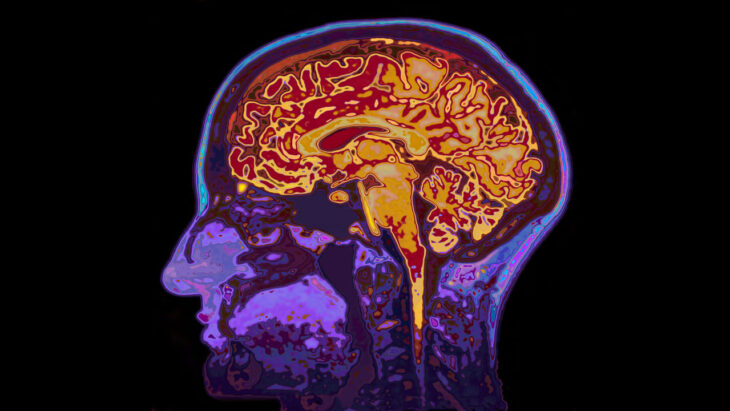

A new study found a key brain area that may contribute to alcohol addiction and an increased risk of relapse, highlighting the importance of alcohol detox and relapse prevention.

Many have wondered why a person continues drinking despite knowing they’re damaging their well-being, relationships and health. Scripps Research scientists discovered a small region in the midline brain plays a key role in the way animals learn to avoid the stress of withdrawal symptoms by continuing to drink.

In animal studies a particular set of brain cells in the paraventricular nucleus of the thalamus (PVT) exhibited increased activity during alcohol withdrawal.

This increased PVT activity appears to amplify the impulse to consume alcohol and may be tied to relapse risk in humans. This discovery underscores why alcohol detox treatment is so important. Without professional withdrawal management, the discomfort and stress of withdrawal can reinforce drinking behavior and increase relapse risk.